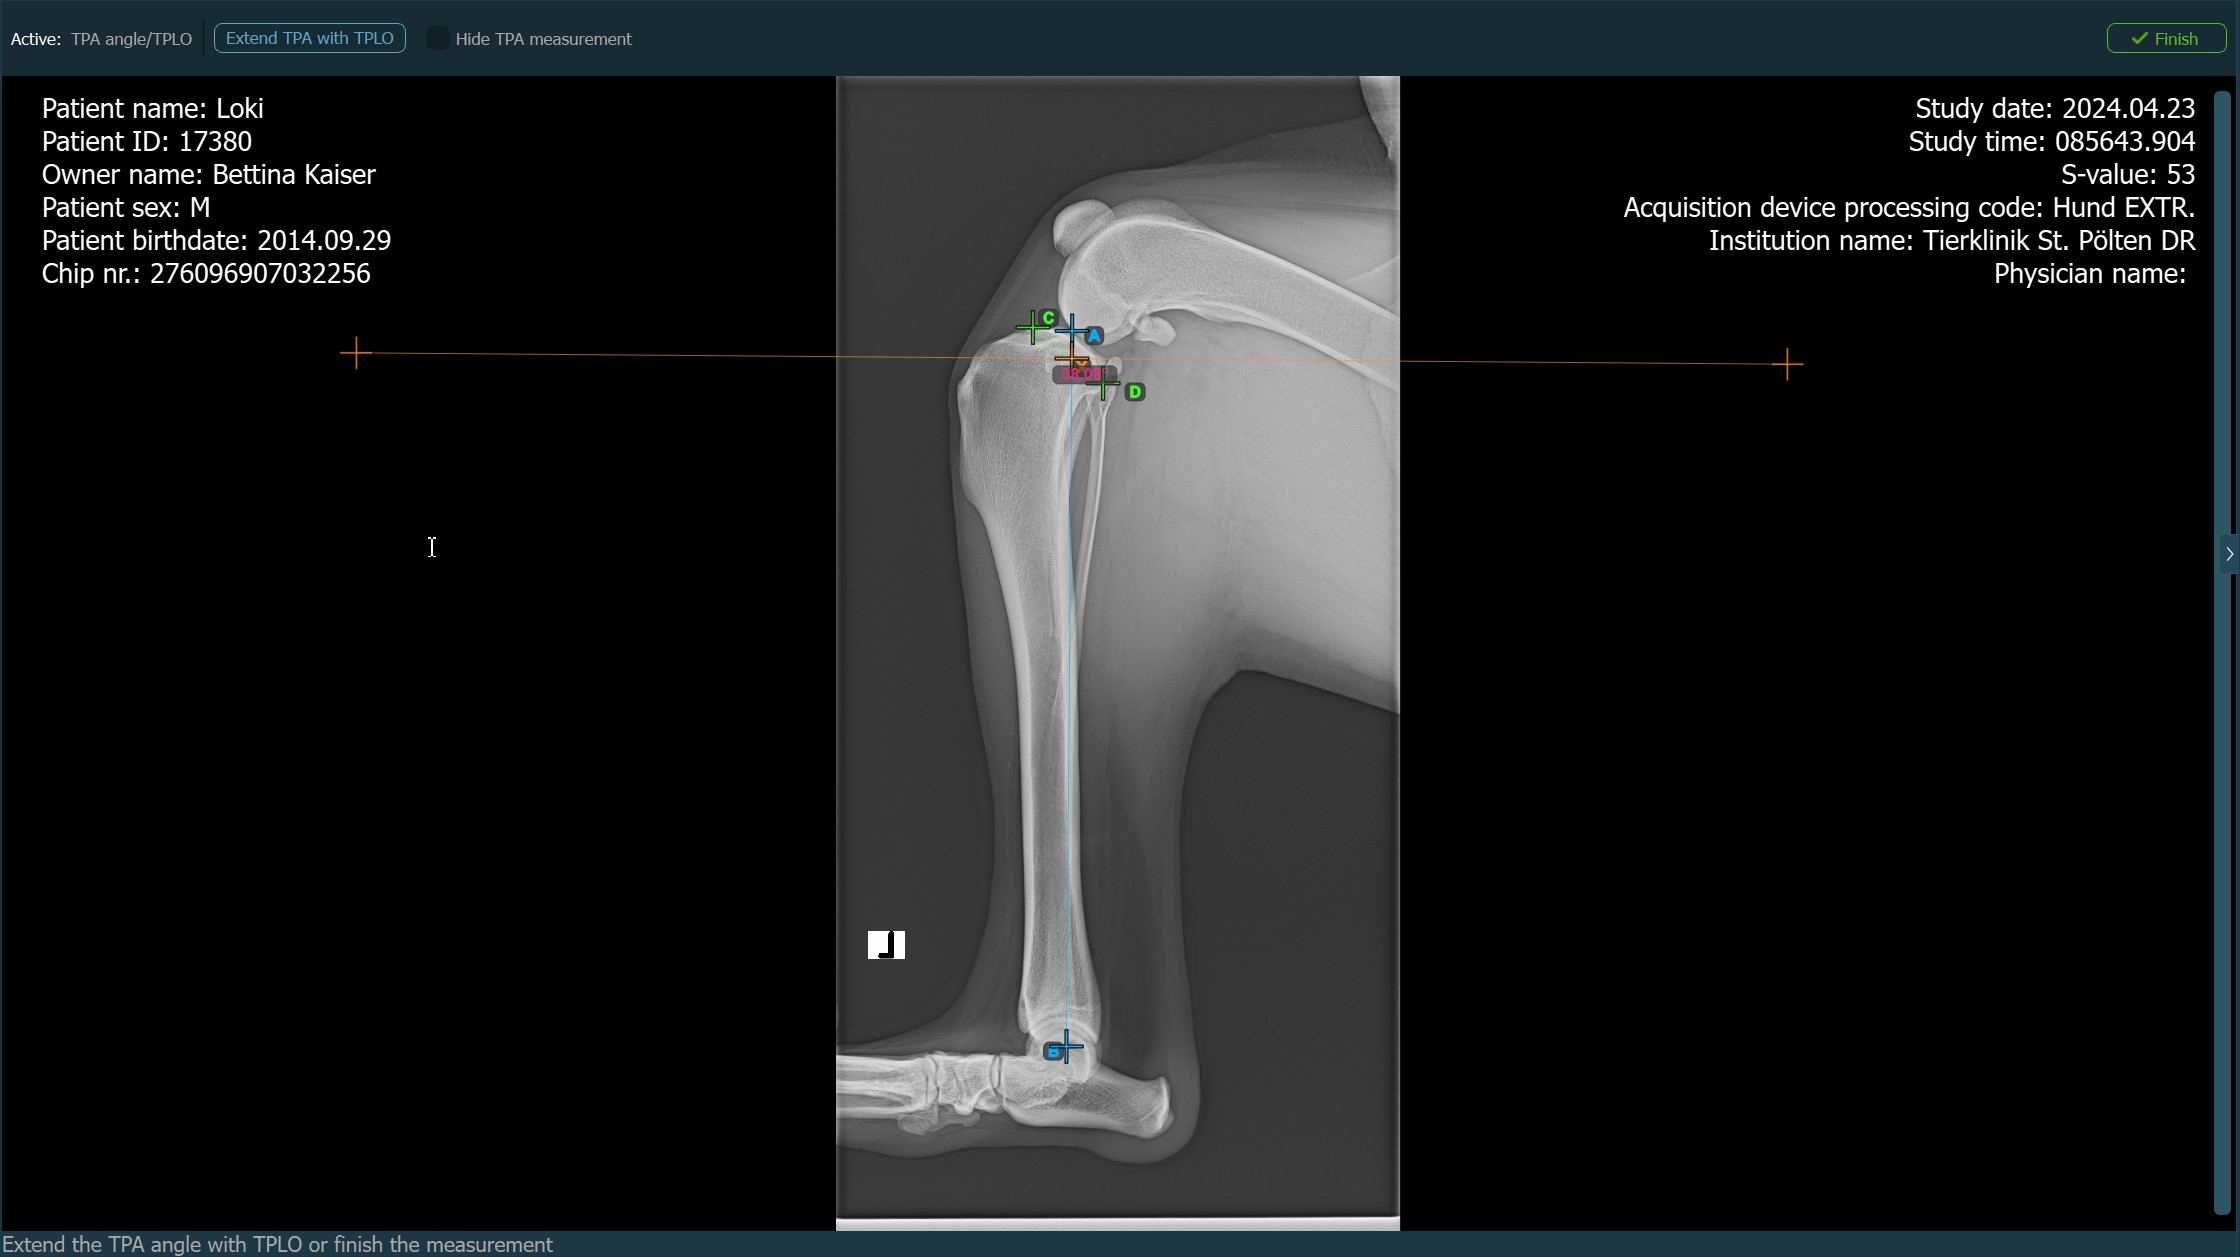

The image below depicts the usual placement of the most caudal point on the tibial plateau and the automatically calculated TPA Angle measurement.

When the TPLO extension to the TPA Angle measurement is enabled, choose one of the available options from the advanced measurement mode toolbar to continue/complete the measurement. The TPA Angle measurement is automatically completed otherwise.

Press

Finishto confirm and complete the TPA Angle measurement without the TPLO extension.Activate the TPLO extension by using the

Extend TPA with TPLObutton.Hide/Show the TPA Angle measurement during the TPLO extension by toggling the

Hide TPA measurementcheckbox.![]()